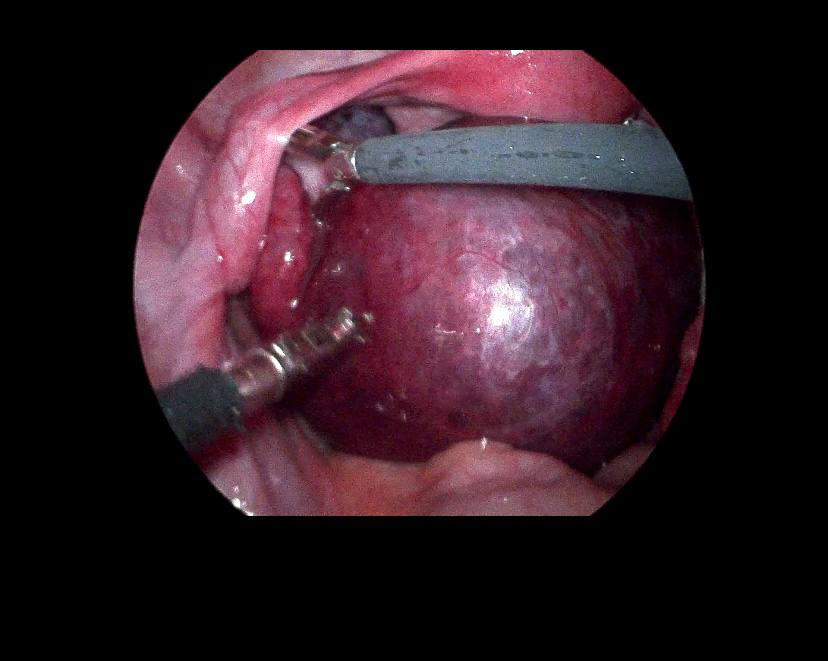

Left ovarian avascular cystic mass 71x68mm , with adjacent left adnexal mass 30x30mm , picture mostly of twisted ovarian pedicle , associated with free fluid >40ml , please for further study to excluded other pathology

Lt ovary is enlarged and edematous, contains 7cm thin wall unilocular cyst “ORADS 1”, there is twisting of its vascular pedicle, picture of ovarian torsion.

operation